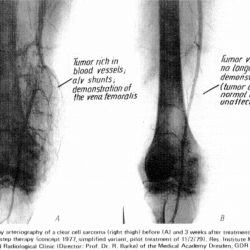

If you are a health care practitioner or researcher, you might be inclined to investigate what Manfred von Ardenne's textbook methodologies might be able to do in a clinical environment that go beyond the sports and life performance aspects we've discussed. Click the image for context.

To expand on this idea in a parallel direction, read the study abstract.

We will leave this without comment save one: The Velocity O2 Training as outlined here is designed as a toolset for exercise physiology in order to to enhance life performance and has NOT been designed with any capability nor is it intended to diagnose, treat, cure or prevent any disease or medical condition. The FDA has not evaluated any statement herein nor this methodology for any such intended purpose.